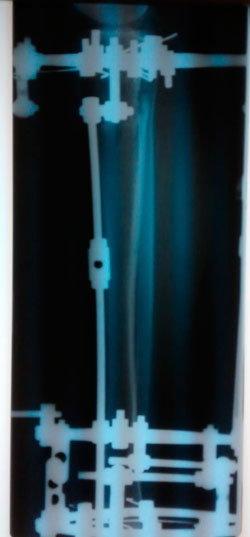

Дата операции - 24.10.2019г.

Дата снятия аппаратов - 22.01.2020

Срок сращения - 89 дней.